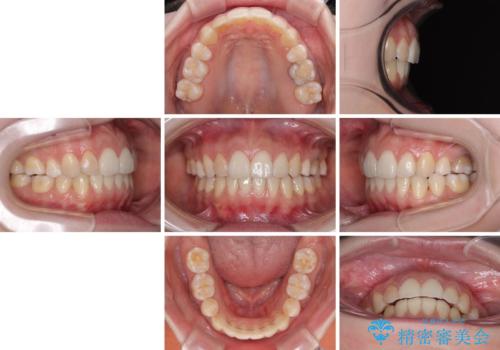

後戻りをインビザラインでスッキリした口元に

- 高校生の時に矯正治療を行ったものの、後取りをしてしまったとのことで来院された患者様です。

マウスピースでもワイヤー矯正でも対応可能でしたが、再度ワイヤーは装着したくないとのことでインビザラインにて矯正治療を行うこととしました。

舌の突出癖が原因で後戻りをしたため、舌のトレーニングをしっかりと行っていただき、口元の突出感を改善することができました。

インビザラインの装着時間が守れず、1年強で終わる予定でしたが、4年間を要することとなりました。